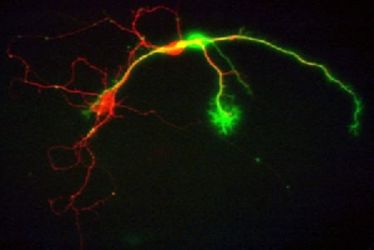

Neurologisches Seminar: Erkenntnisse aus der Neurogeneseforschung und Implikationen für die Klinik

Neurologisches Seminar: Erkenntnisse aus der Neurogeneseforschung und Implikationen für die Klinik